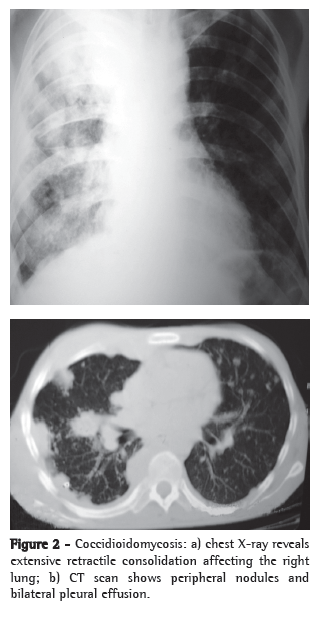

The most common form of presentation of coccidioidomycosis, primary pulmonary coccidioidomycosis is characterized by pulmonary manifestations that generally appear one to three weeks after exposure to the fungus. Approximately 60% of the infected individuals evolve to spontaneous cure without clinical or radiological manifestations. The remaining 40% generally present symptoms of acute respiratory disease, mimicking the flu, accompanied by fever, night sweats and cough or pleuritic chest pain, or a combination of the two. The manifestations appear between 10 and 15 days after exposure to the fungus, and the intensity of the symptoms depends directly on the infective load, ranging from the flu to a severe, nonspecific respiratory infection, accompanied by high fever, chest pain and cough with or without expectoration, as well as by general symptoms or allergic manifestations, particularly erythema nodosum. Primary pulmonary coccidioidomycosis generally resolves spontaneously within 30-60 days, even without antifungal treatment. However, approximately 5% of these patients develop residual pulmonary lesions (generally solitary nodules) that are asymptomatic in most patients. These cases are often diagnosed after surgical removal due to suspected lung cancer. Another 5% of these patients develop thin-walled cavities, solitary and juxtapleural, that might resolve spontaneously in approximately 2 years. In certain cases, principally in diabetic or immunocompromised patients, the acute pulmonary form does not resolve; it progresses to chronic pneumonia and is characterized by the formation of pulmonary cavitation. The lungs might also be diffusely affected as a result of the inhalation of a large quantity of infective arthroconidia or as a late and secondary presentation resulting from hematogenous dissemination. These forms present with multiple diffuse infiltrates, the largest of which might present cavitation accompanied by severe respiratory manifestations, which can lead to respiratory failure and are more commonly observed in immunocompromised patients. The disease might progress to death, mimicking septic shock, accompanied by acute respiratory distress syndrome, with high mortality rates.(13,27)

Nonspecific tests that are useful for the evaluation of patients include X-rays and CT scans of the affected site, principally of the chest, and can greatly aid in the diagnosis (Figures 2 and 3). The most common findings on chest X-rays are multiple lung nodules of peripheral distribution, associated with parenchymal consolidation. CT scans of the chest reveal peripheral lung nodules that are predominantly cavitated.(29,39)